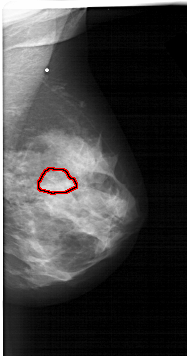

A_1566_1.LEFT_MLO

LEFT_MLO LINES 6346 PIXELS_PER_LINE 3751 BITS_PER_PIXEL 12 RESOLUTION 43.5 NON_OVERLAY

FILE: A_1566_1.RIGHT_MLO.OVERLAY

TOTAL_ABNORMALITIES 1

ABNORMALITY 1

LESION_TYPE MASS SHAPE LOBULATED MARGINS OBSCURED

ASSESSMENT 4

SUBTLETY 3

PATHOLOGY BENIGN

TOTAL_OUTLINES 1

BOUNDARY